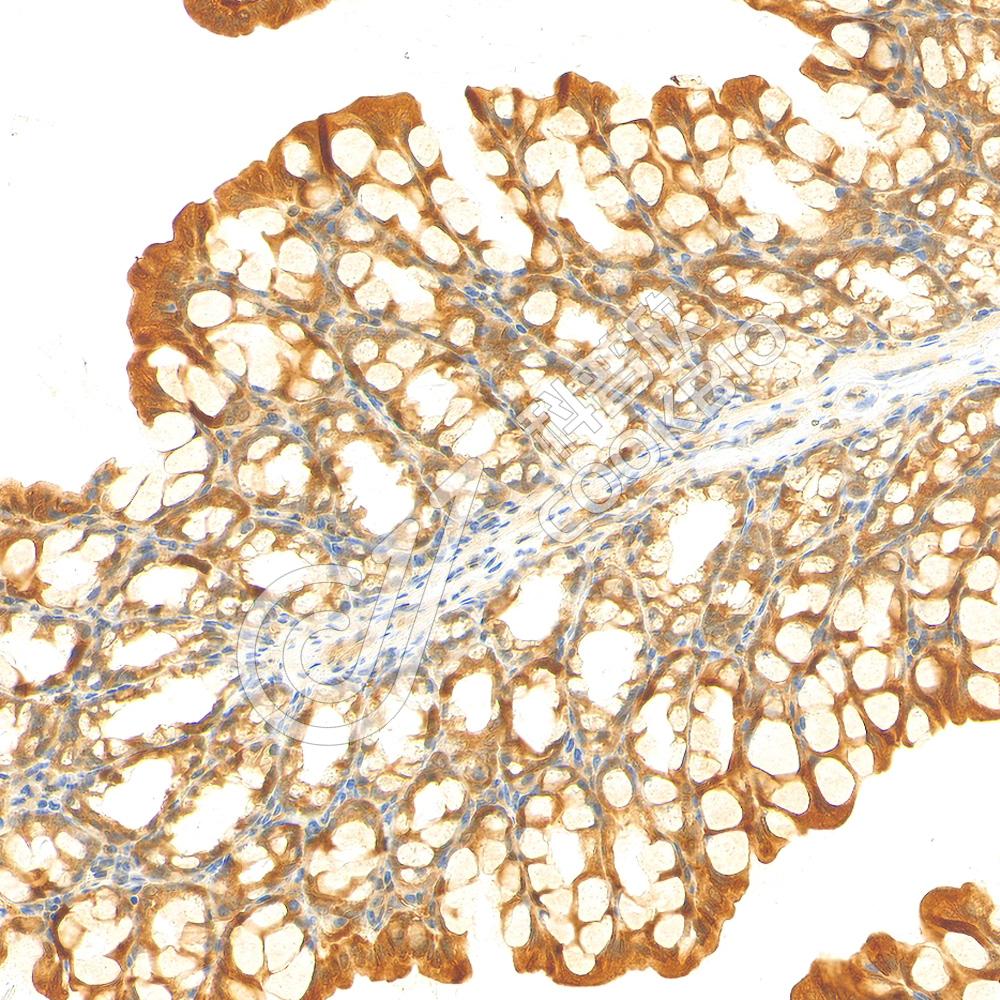

IHC检测GSDMD蛋白(货号 K5462594).

样品: 小鼠lps(6h)诱导的结肠炎症模型, 4%多聚甲醛 (货号KSG1101) 固定12-24小时.

抗原修复: Tris-EDTA抗原修复液(pH 9.0) (KSG1203), 98℃, 20分钟.

—抗: 1: 1500稀释, 4℃ 孵育过夜.

二抗: S-vision免疫组化多聚二抗(山羊抗兔),即用型 (货号KB3906), 室温孵育20分钟.